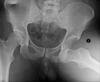

5

Intracapsular NOF